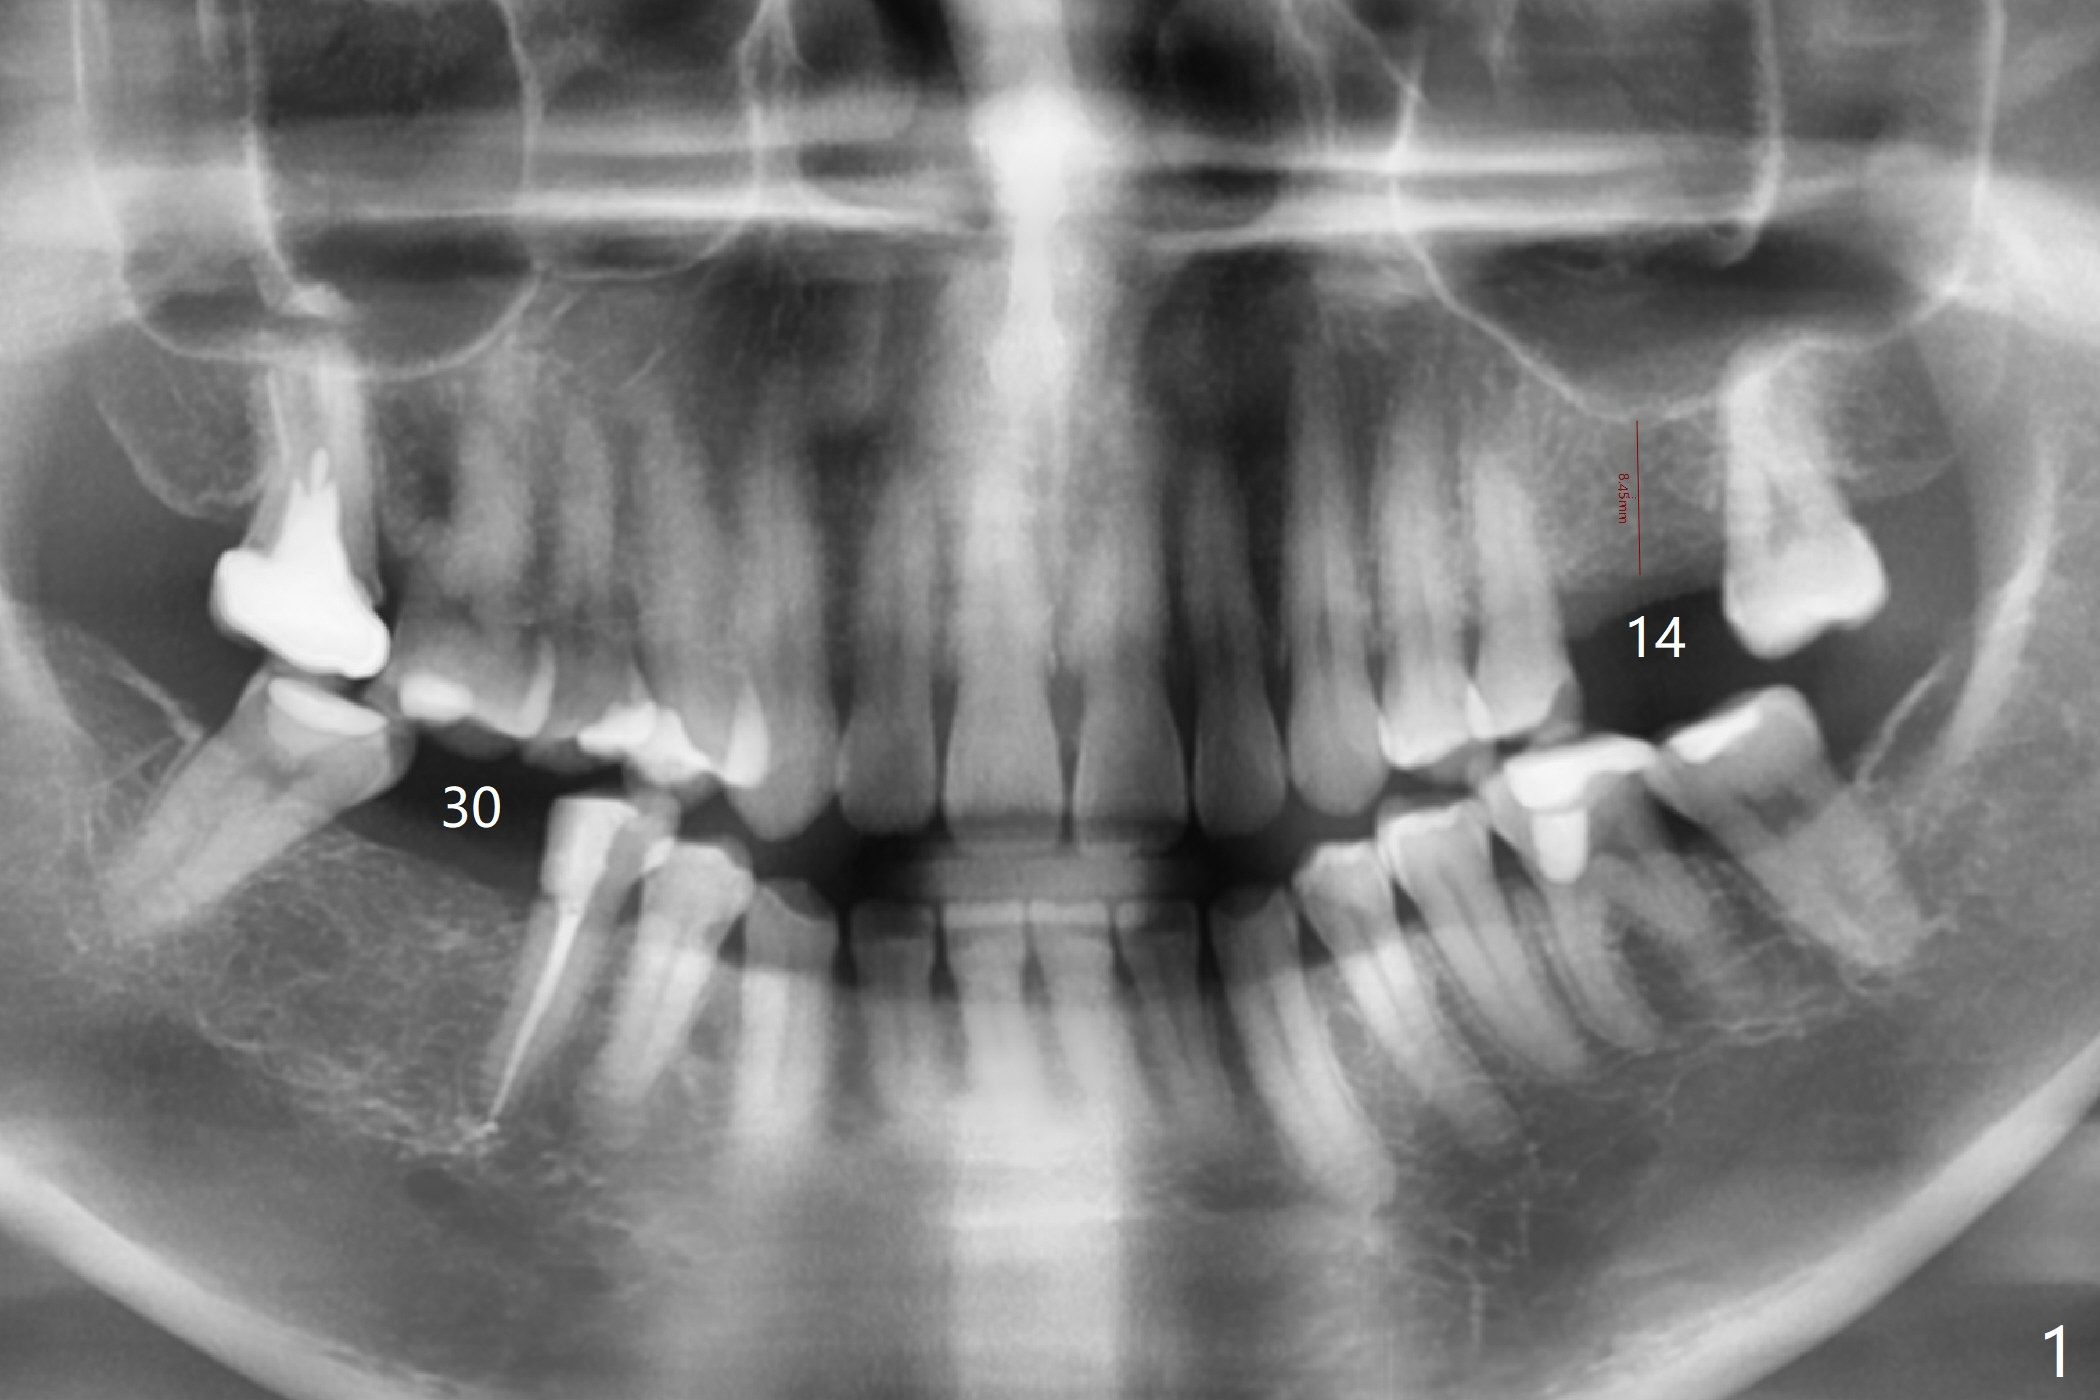

Guided Surgery for Fearful Patient

A 49-year-old woman is afraid of dentistry. To reduce anxiety, guided surgery is planned for #30 first (Fig.1,2). Lab designs a 5x10 mm implant instead of 5x11.5 mm for safety (Fig.2). Review guided surgery protocol. Irrigate well while drilling early and rinse thoroughly osteotomy site after each drill later. The bone is dense. Slow down drilling to reduce heat and postop pain. In fact, the surgery is finished in 10 minutes.

The bone height at #14 is 8.45 mm (Fig.1').